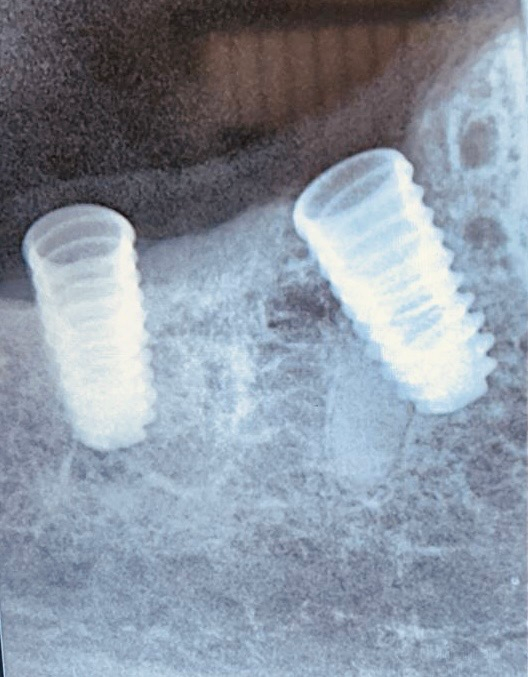

The various prosthetic treatment options for malpositioned implants are outlined in Table 1. Malpositioned implants may result from multiple surgical and prosthetic errors; Figures 1–3 highlight the various positional errors encountered in dental implant placement.

Figure 2. Closely placed implant impression copings.